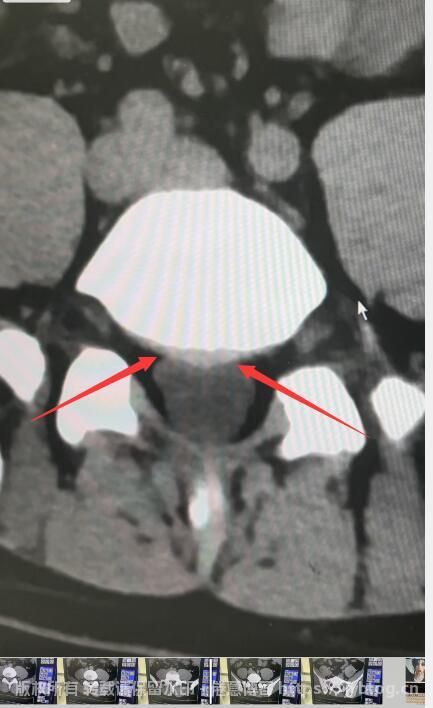

腰椎间盘突出症,也被认为是一种脊柱退行性疾病,是主要引起腰痛和腿痛的常见原因。此疾病的发病原因通常来自腰椎间盘的退变,当纤维环部分或全部断裂时,髓核突出会刺激或压迫神经根,马尾神经,导致疼痛和其他症状。患者通常有长期弯腰劳动或长时间坐立的经历。患病率高的人群包括儿童、青少年、投掷、跳高、跳远等运动员,驾驶员,老年人,孕妇和有家族史的人。

说大白话,弯腰太多,把椎体和椎体之间的椎间盘给挤出来了,如果压迫到神经根,就会引起症状,比如腰痛啊,屁股痛啊,小腿酸胀,严重的还会出现麻木的症状。

还好发现的早,目前除了腰酸没有什么其他的症状。󠄐󠄹󠅀󠄪󠄢󠄡󠄦󠄞󠄧󠄣󠄞󠄢󠄡󠄦󠄞󠄡󠄡󠄣󠄬󠅒󠅢󠄟󠄮󠄐󠅅󠄹󠄴󠄪󠄾󠅟󠅤󠄐󠄼󠅟󠅗󠅙󠅞󠄬󠅒󠅢󠄟󠄮󠅄󠅙󠅝󠅕󠄪󠄡󠄧󠄦󠄡󠄨󠄦󠄠󠄩󠄨󠄤󠄬󠅒󠅢󠄟󠄮